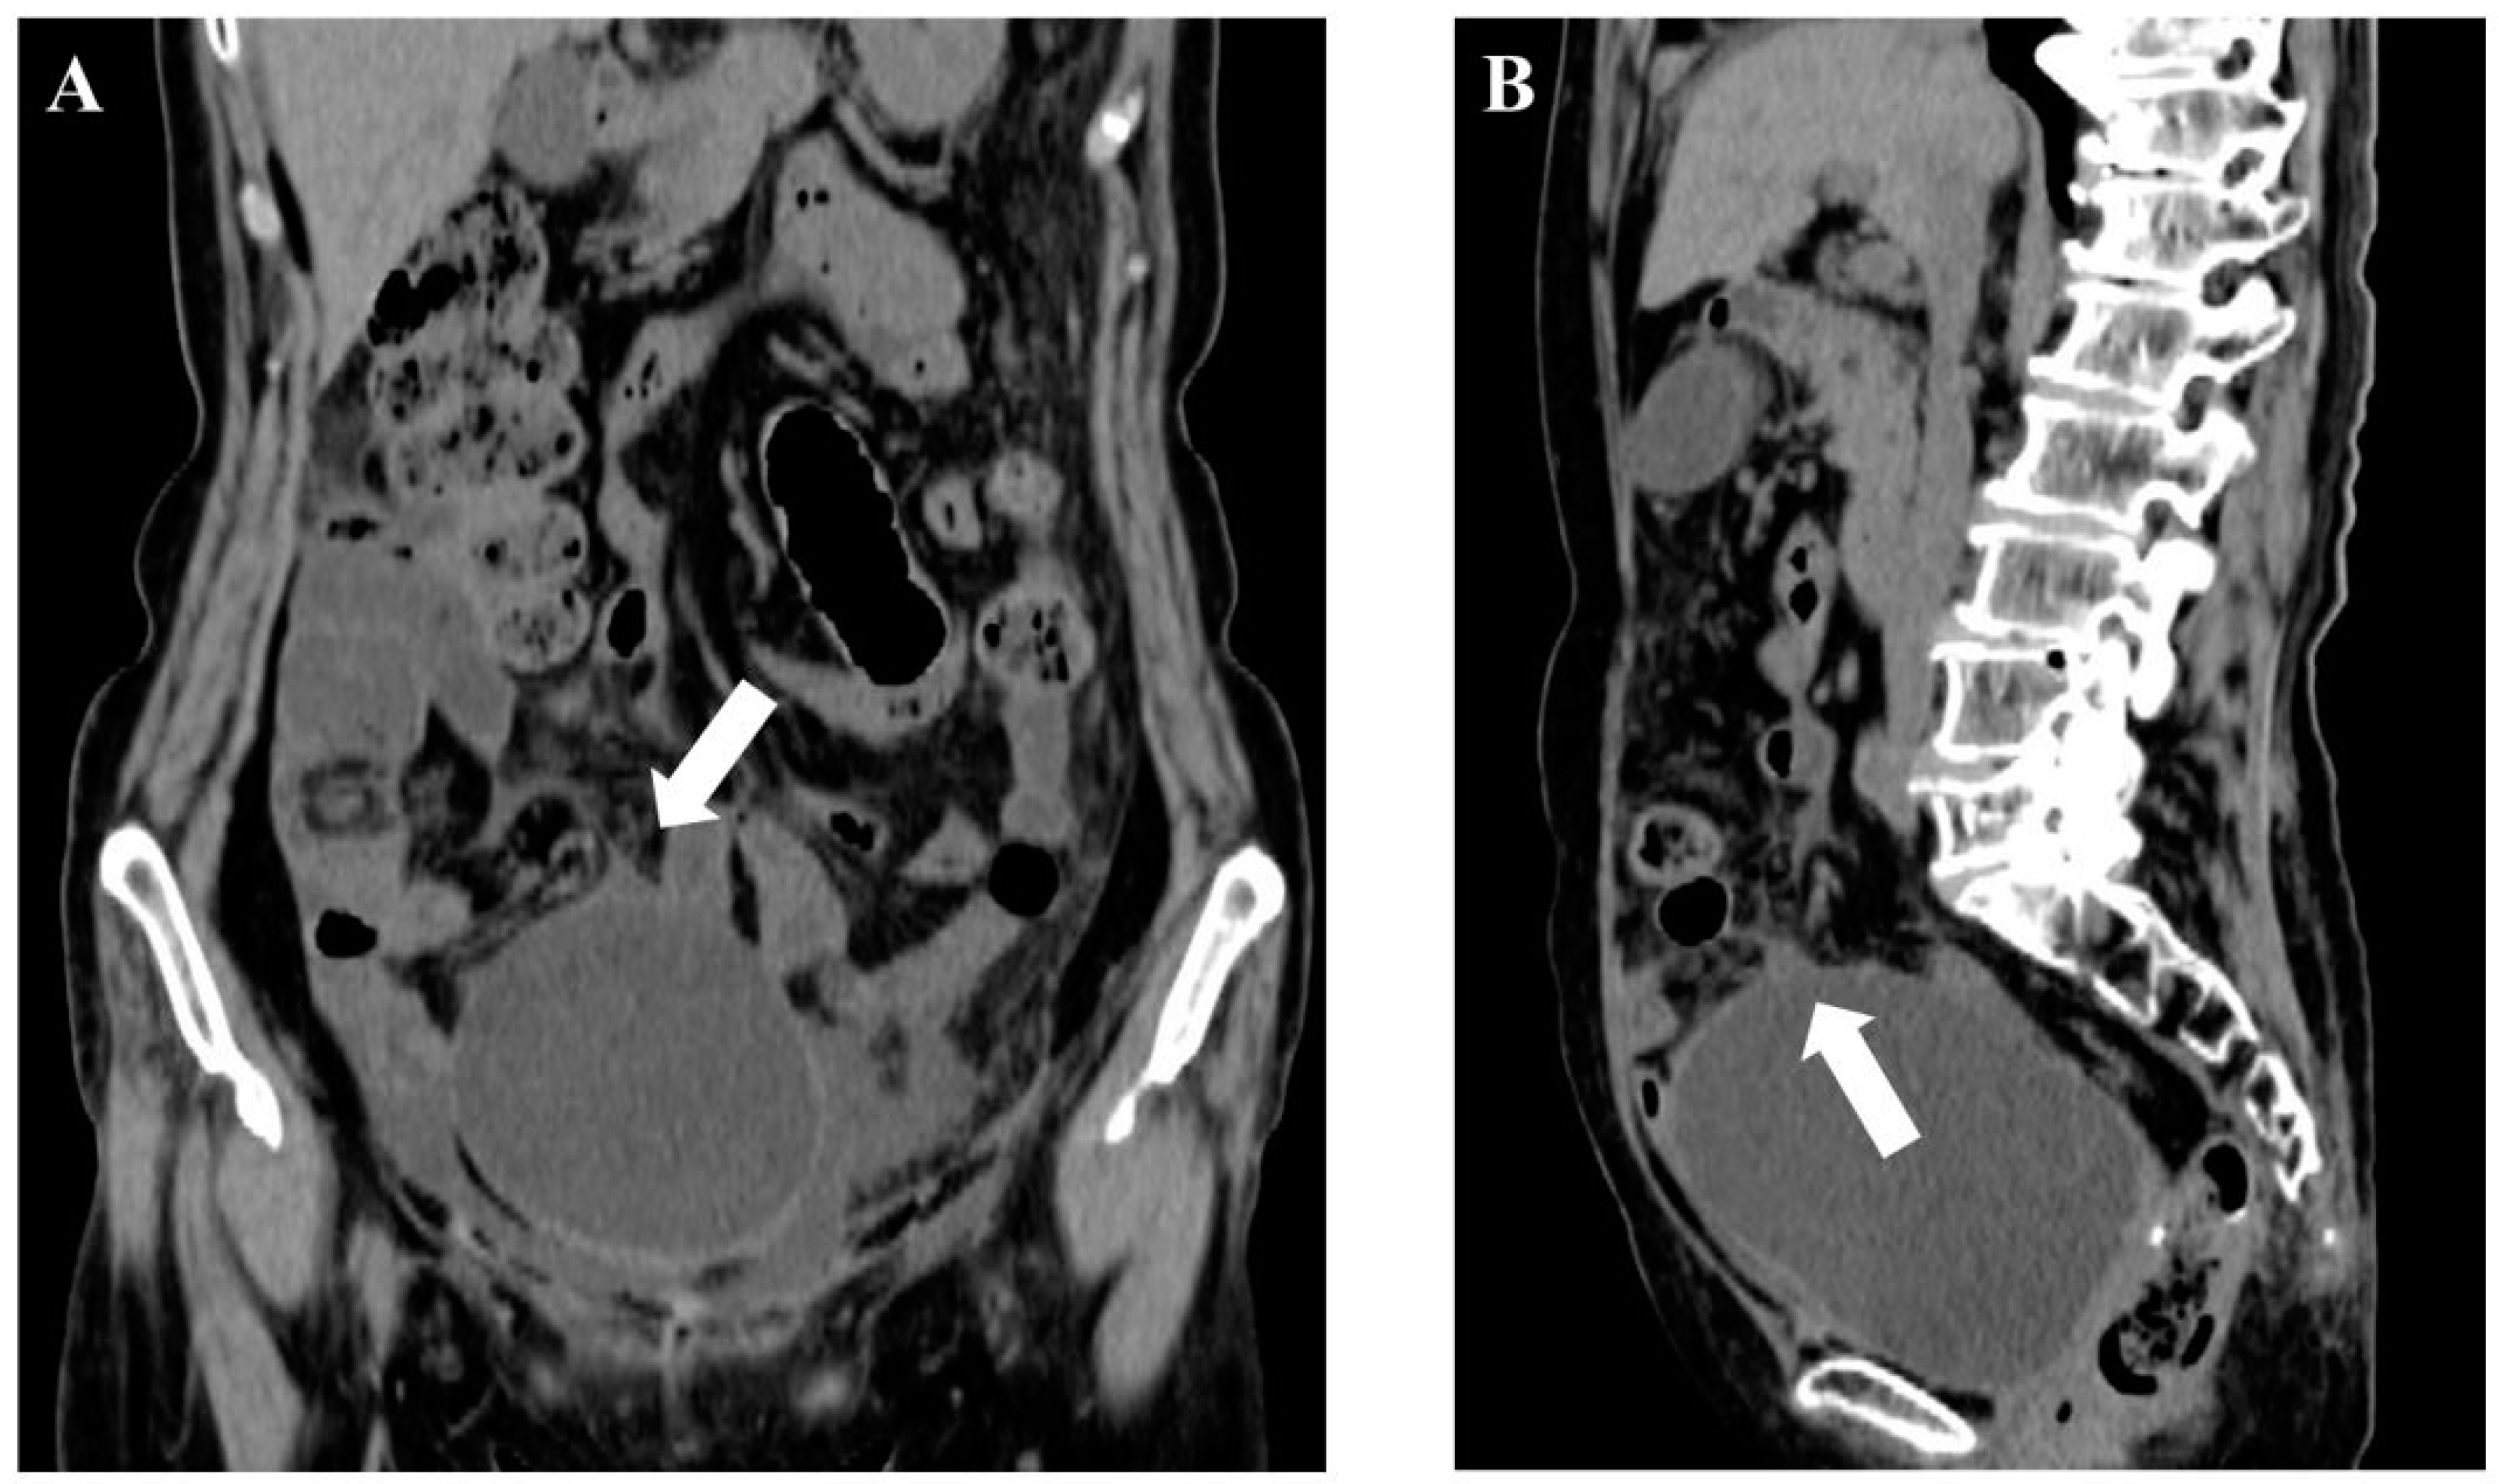

2. Case Report